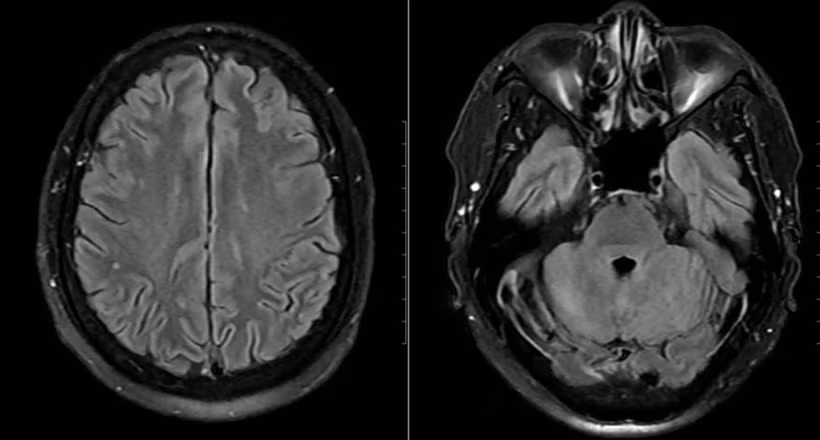

Hình ảnh chụp tổn thương não của bệnh nhân.

Mặc dù chưa có biểu hiện thần kinh rõ ràng, bệnh nhân vẫn được chọc dò dịch não tủy để loại trừ biến chứng. Kết quả cho thấy dịch não tủy có tăng tế bào và protein, phản ứng Pandy dương tính, xác định viêm não-màng não. Bên cạnh đó, hình ảnh MRI sọ não phát hiện ổ tổn thương nhỏ tại thùy chẩm trái.